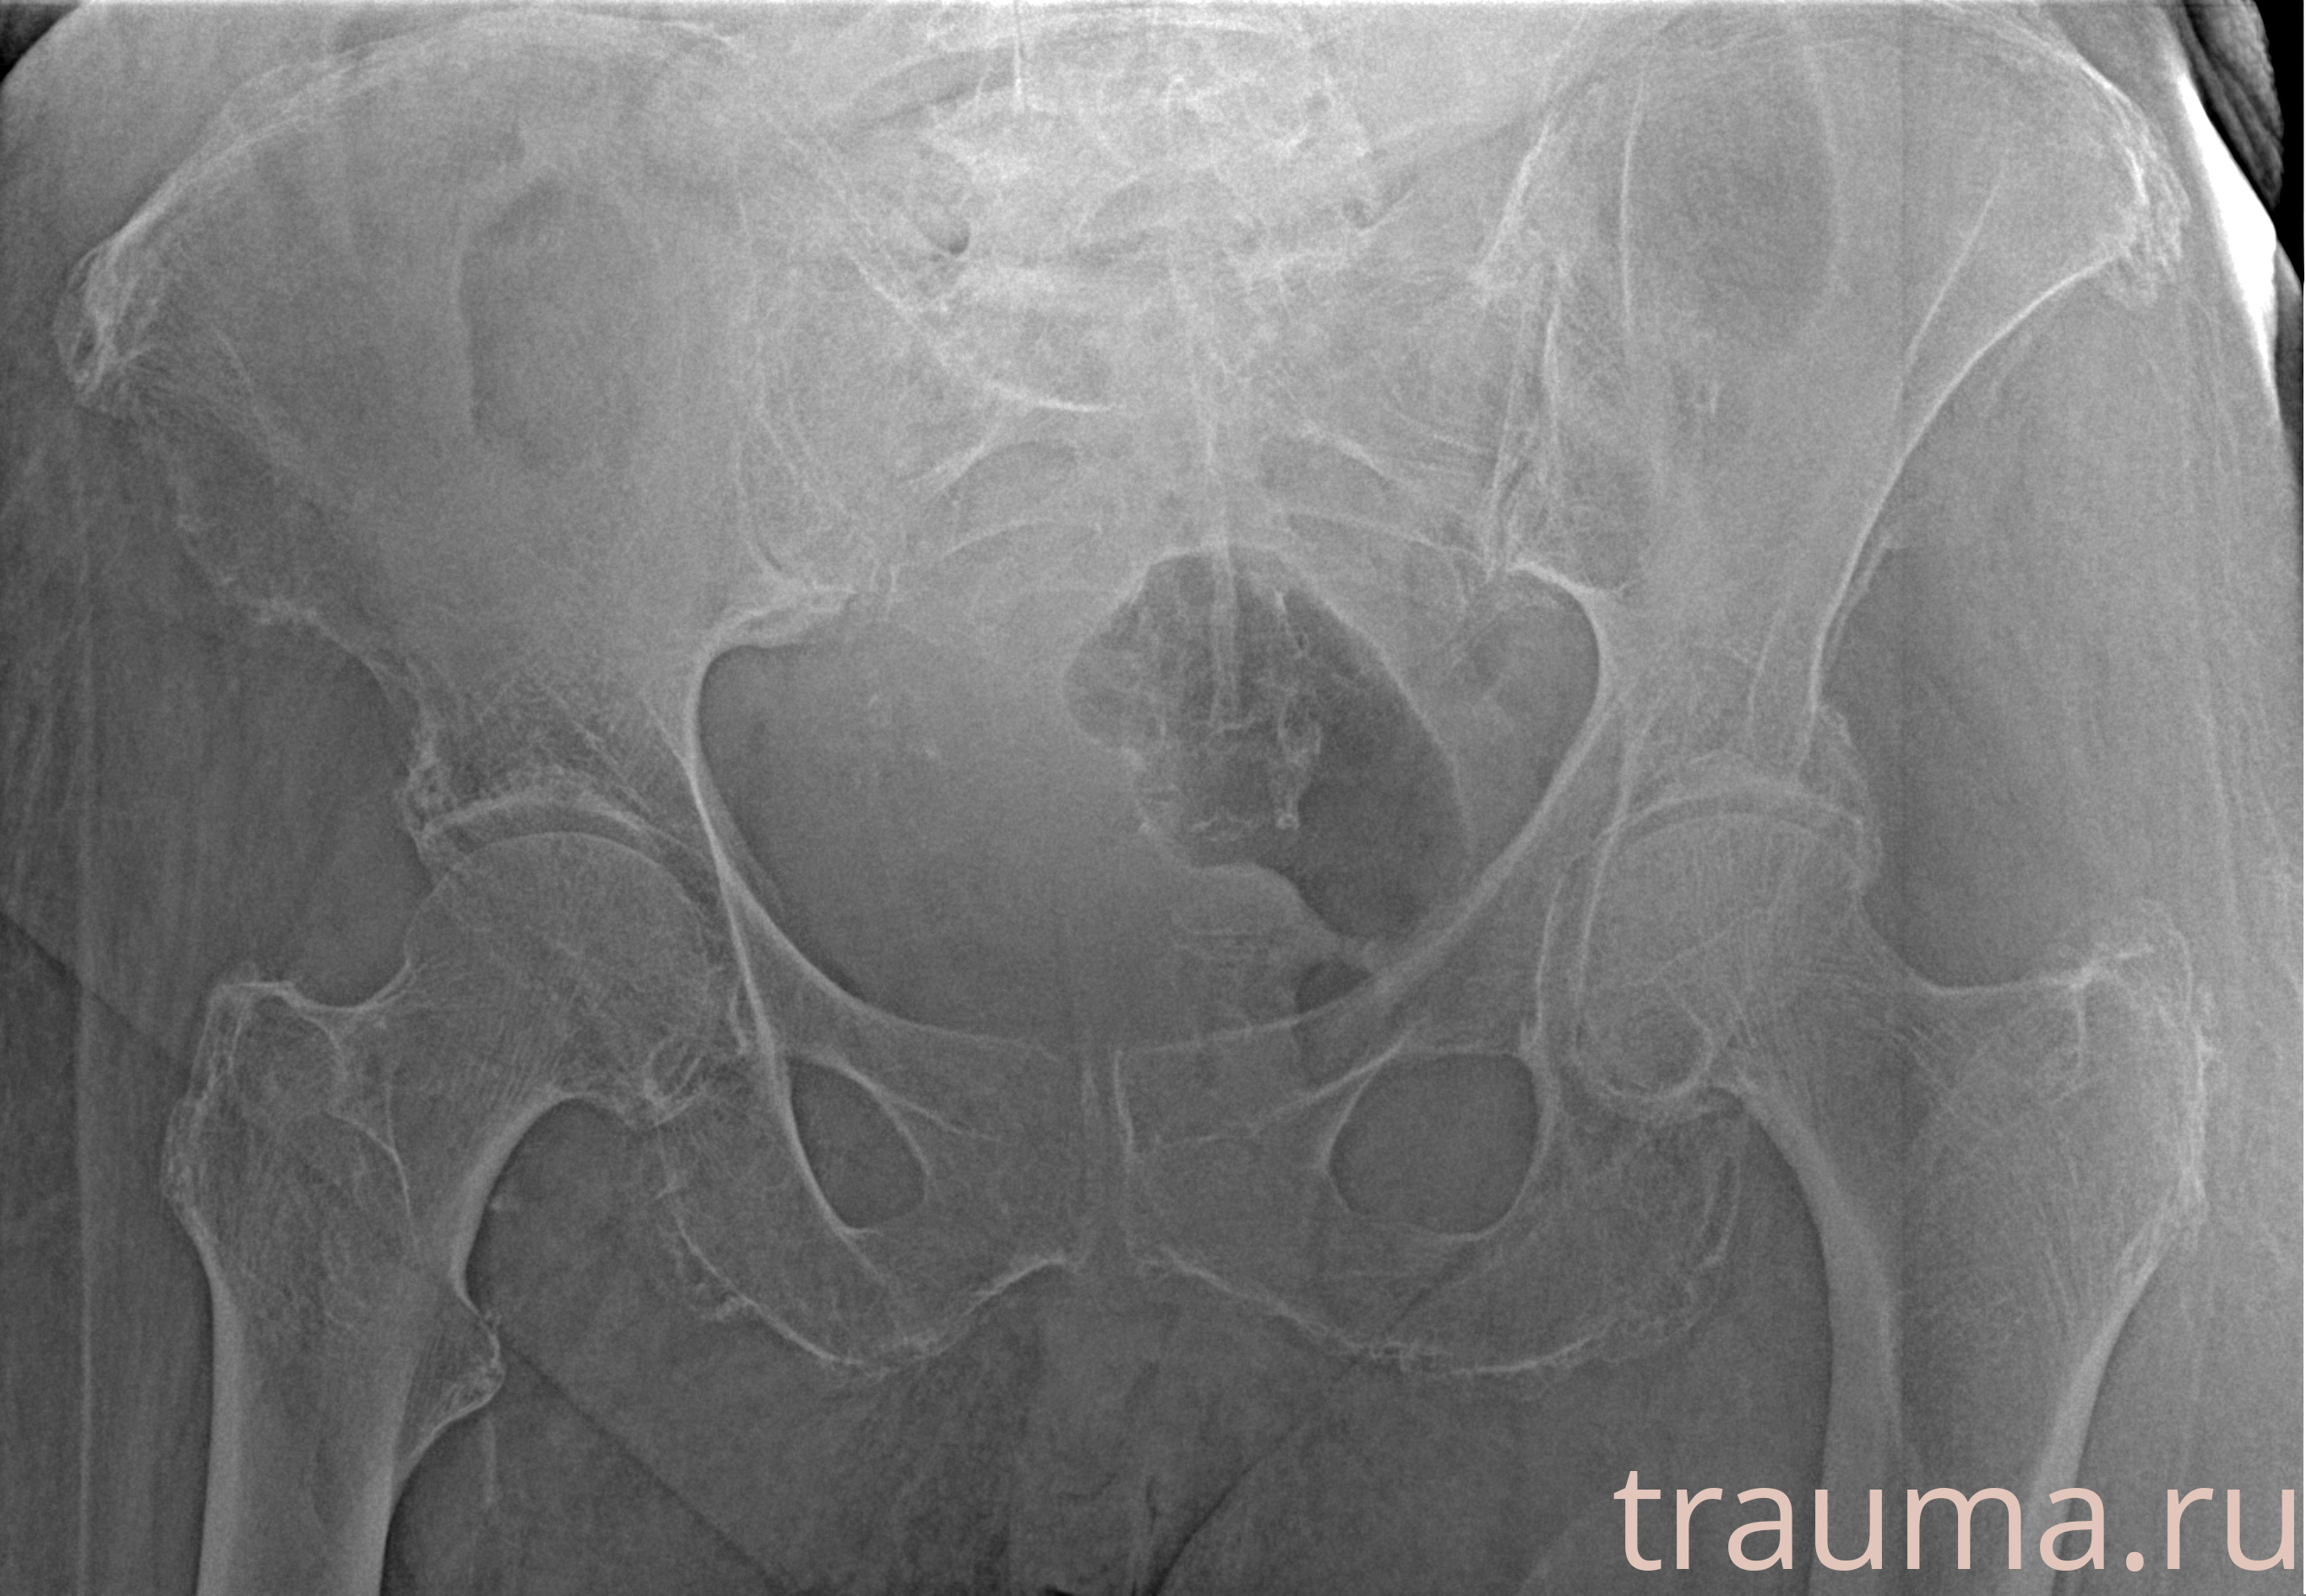

Рентгенограммы

Рентген на дому: по вашему адресу приезжает врач-рентгенолог, травматолог-ортопед с мобильным рентгеновским аппаратом, проводит диагностику травмы или заболевания, делает необходимые рентгенограммы, дает рекомендации по дальнейшему лечению. Получить качественные снимки в домашних условиях возможно благодаря уникальной методике, разработанной МосРентген Центром для института  Склифосовского